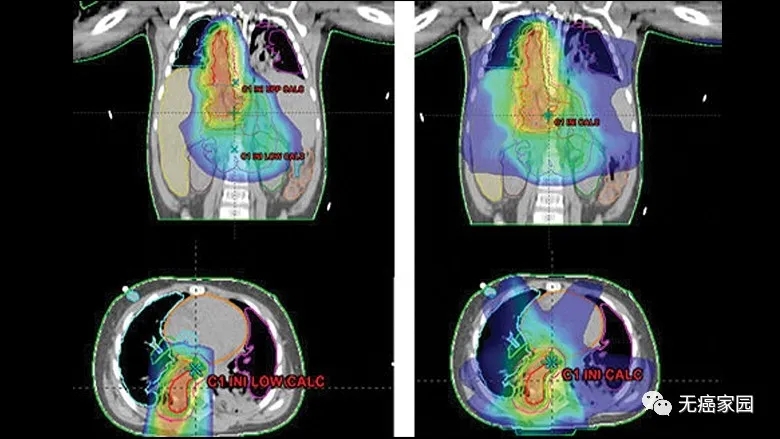

使用质子(左)与X射线治疗(右) 质子治疗对周围重要器官损伤更少